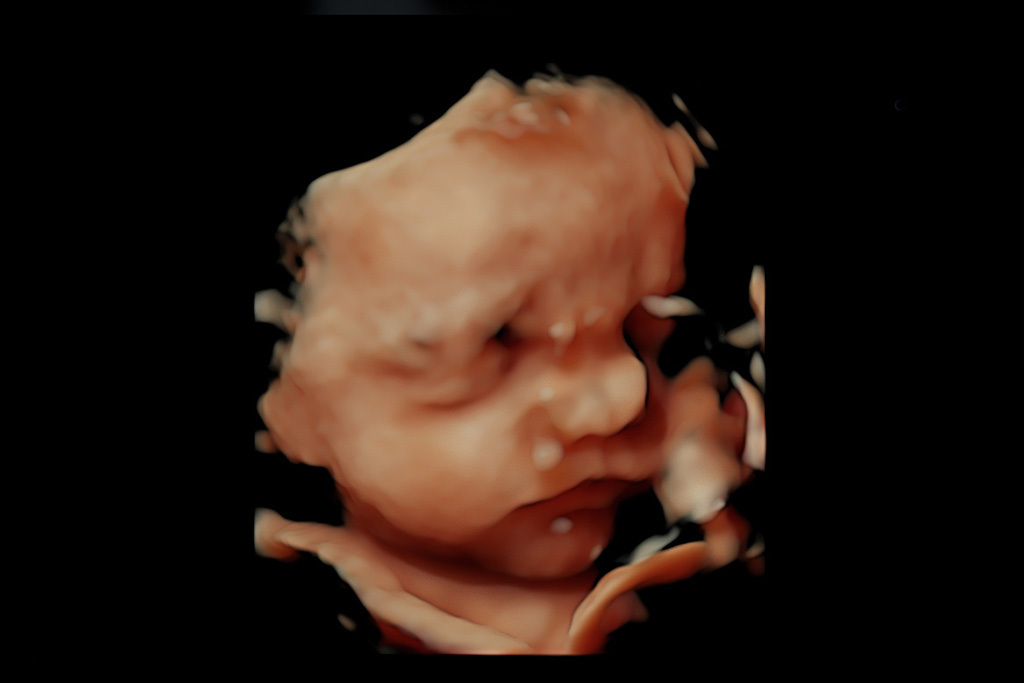

Ecografía 3D

La Ecografía 3D permite la obtención de imágenes en 3 dimensiones en alta calidad y a color que nos permiten ver detalles anatómicos del bebé en 3D como el perfil fetal, la forma de los labios, las extremidades, la nariz y los ojos, entre otros.